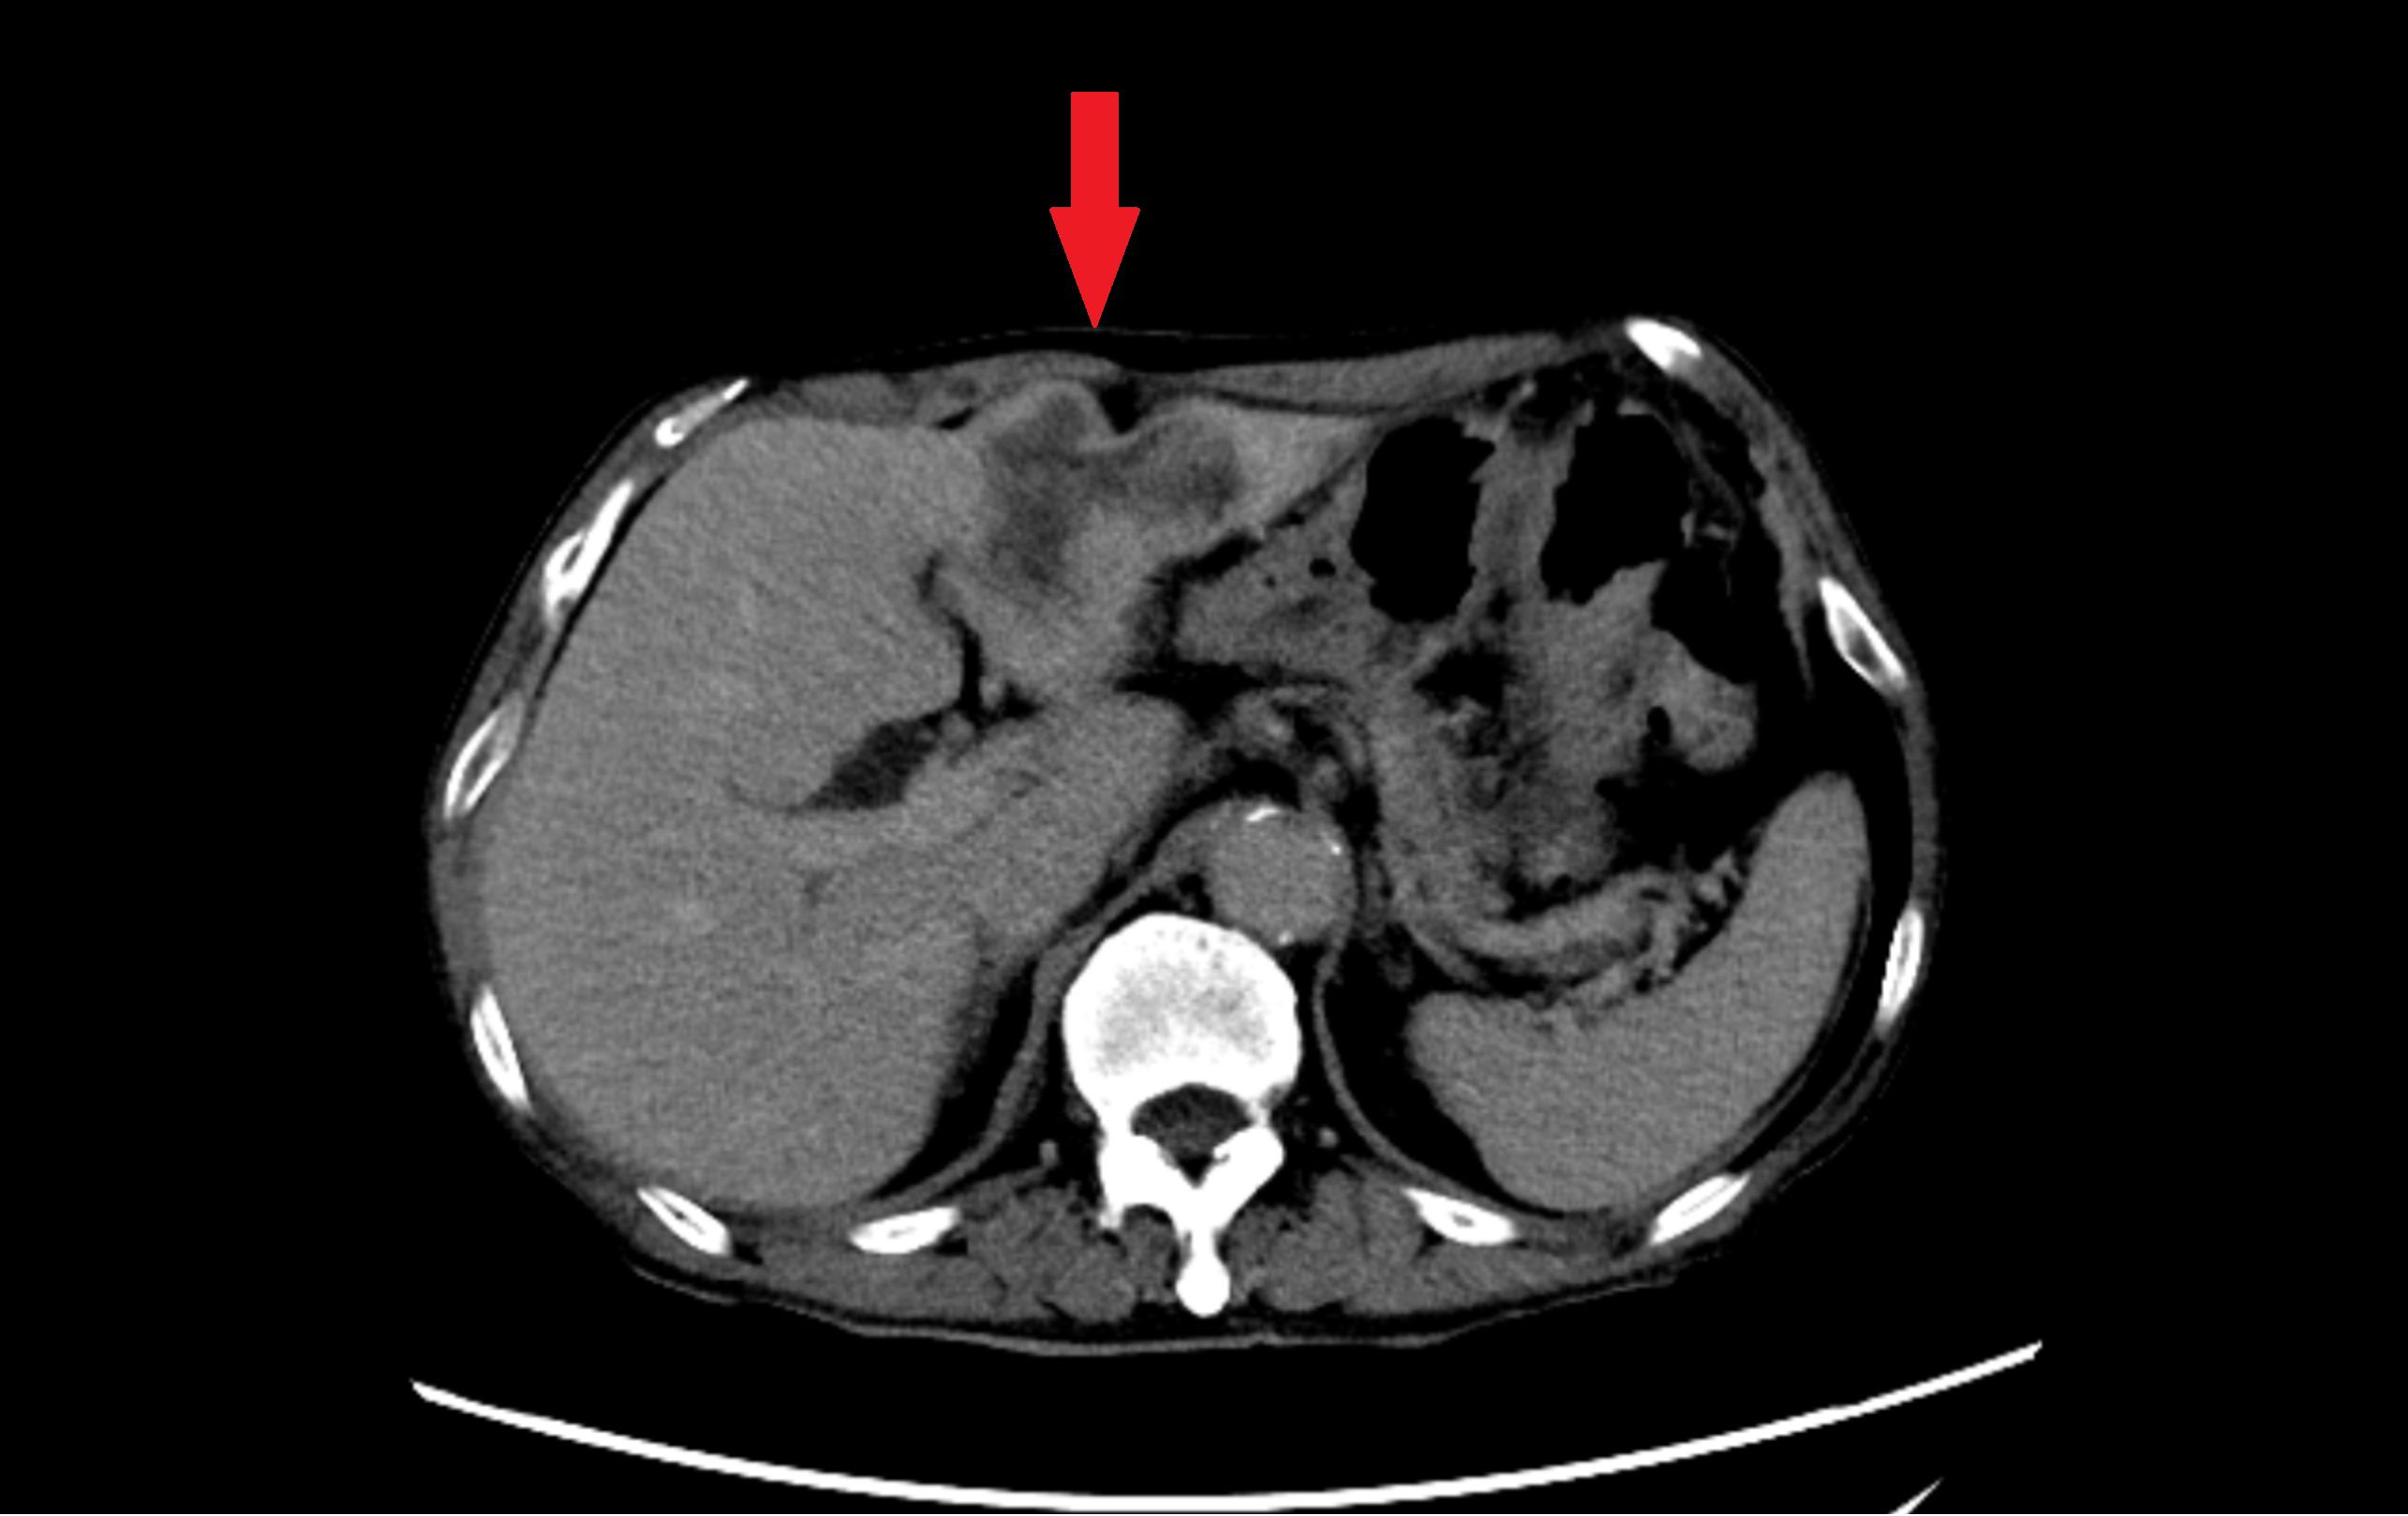

More than 1 month ago, the patient was admitted to the local hospital because of increasing abdominal pain lasting for 22 days, and ultrasound and abdominal CT revealed a space-occupying lesion in the left lobe of the liver (Figure 2). 17 days ago, a liver puncture was performed in our hospital, and the pathology showed adenocarcinoma. Meanwhile, serum tumor marker profiling revealed significantly elevated preoperative levels of CA125(59.3 U/mL), CA19-9(1355 U/mL), and CA15-3(36.1 U/mL). 8 days ago, laparoscopic left hemihepatectomy with abdominal lymph node dissection was performed under general anesthesia, and the pathology showed intrahepatic cholangiocarcinoma after the operation. The final oncological diagnosis of the patient was intrahepatic cholangiocarcinoma, with a stage of T2bN1M0, and it was classified as stage IIIB. Postoperative assessment demonstrated marked reduction in all three markers, with CA125(32.8 U/mL, reference range<35.0) and CA15-3(12.6 U/mL, reference range ≤ 25.0) normalizing to reference ranges. Other tumor markers remained within normal limits. Five weeks after the surgery, the patient began the first cycle of adjuvant chemotherapy. After chemotherapy, bone marrow suppression occurred. The blood routine test conducted at another hospital showed severe reduction in neutrophils and platelets. The patient was hospitalized at that hospital for platelet transfusion and the subsequent chemotherapy plan was suspended.

Figure 2. Abdominal contrast-enhanced CT in the equilibrium phase. Axial imaging demonstrates an irregular, heterogeneously enhancing mass in the left hepatic lobe (red arrow), accompanied by adjacent bile duct dilatation.